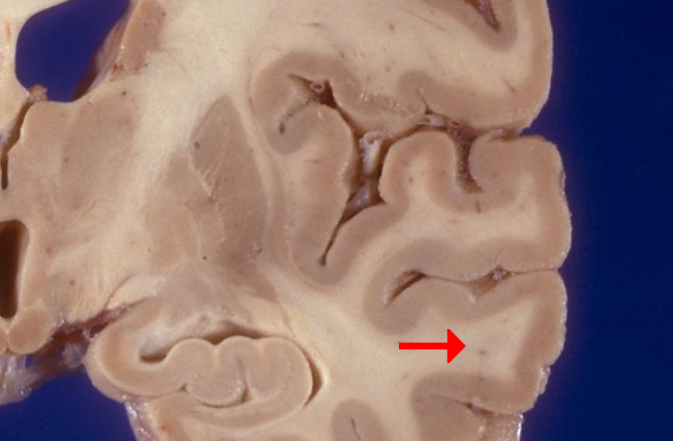

Label this brain structure

Superior colliculi

Name this brain structure

Fornix

Label this brain structure

Pineal gland

Label this brain structure

Sylvian fissure

Label this brain structure

Superior temporal gyrus

Label this brain structure

Middle temporal gyrus

Label this brain region of the temporal lobe

Inferior temporal gyrus